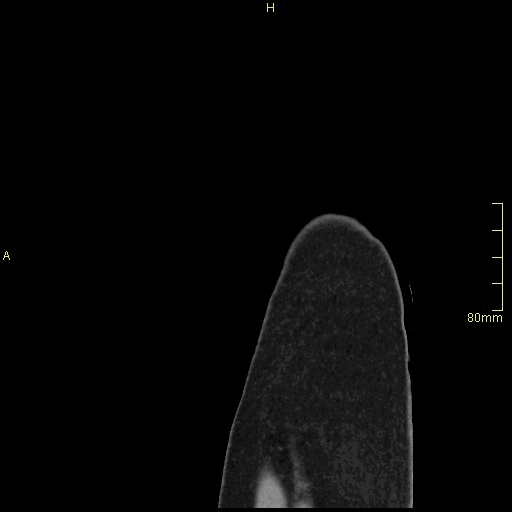

CT Urogram Non Contrast (Sagittal)